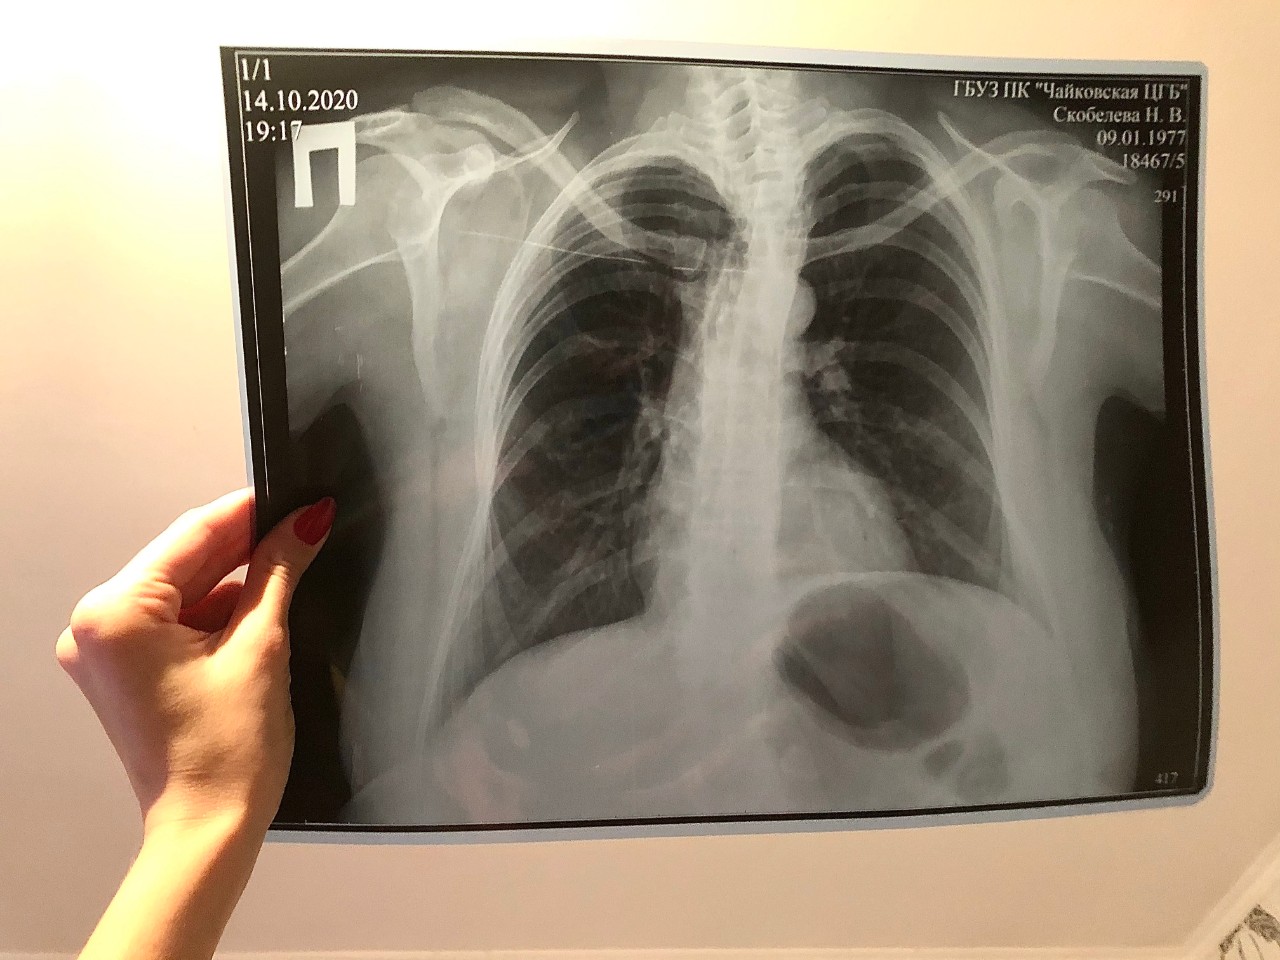

Нормальная рентгенограмма легких: что нужно знать